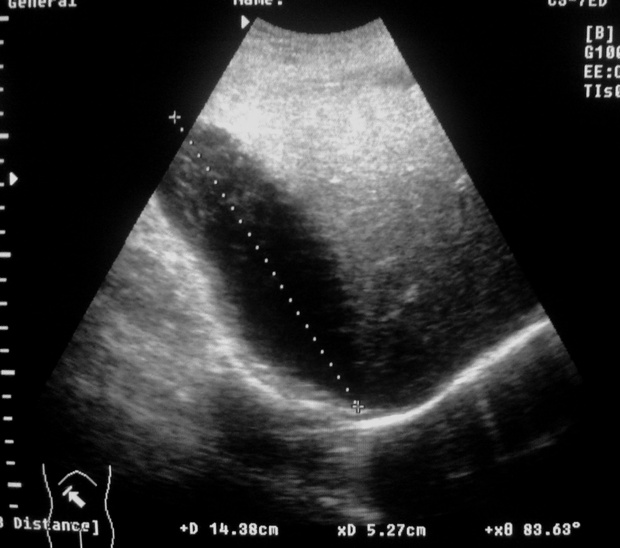

Снимки 2-3 - не в брюшной ли полости жидкость?

Жидкости в брюшной полости не обнаружено. После УЗИ больной переведен в хирургическое отделение.

После Rtg пневмонию исключили.

Жидкость в БП не обнаружена?

Что это есть такое?

Травма+анемия+ЭТО =?

Если маркеры стоят правильно, то это поддиафрагмальная внутрибрюшная гематома.

Возможно и внутрибрюшная, а может и подкапсульная гематома. Кстати, каковы критерии диф.диагноза?